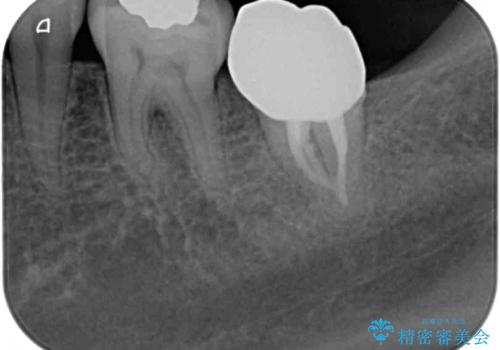

その後、左上の奥歯にも咬合時の痛みが認められ、レントゲン写真より歯内の神経が失活していることが分かりました。

2歯ともに根管治療を行い、その後はオールセラミッククラウンにて補綴治療を行うこととしました。